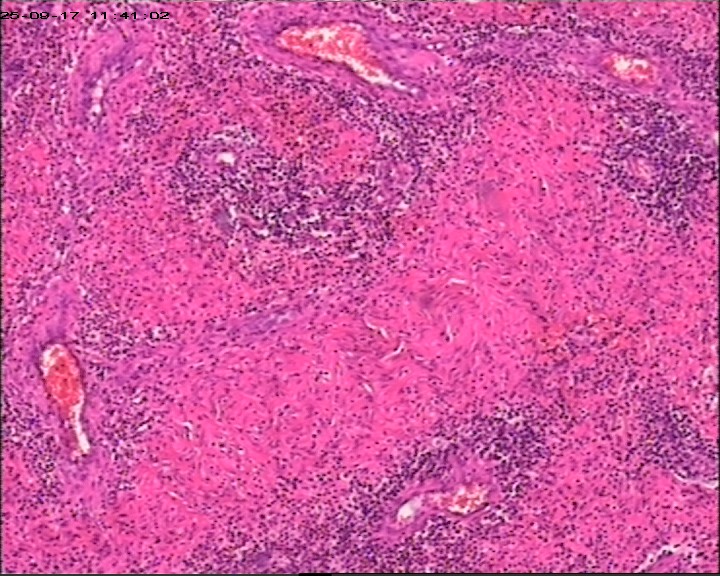

臀部组织,请帮忙看看,谢谢

性别

男

年龄

20岁

临床诊断

一般病史

藏毛窦或囊肿切开术

标本名称

臀部

大体所见

灰白灰黄碎组织一堆,大小为6.5*4*1cm。

描述诊断炎性病变